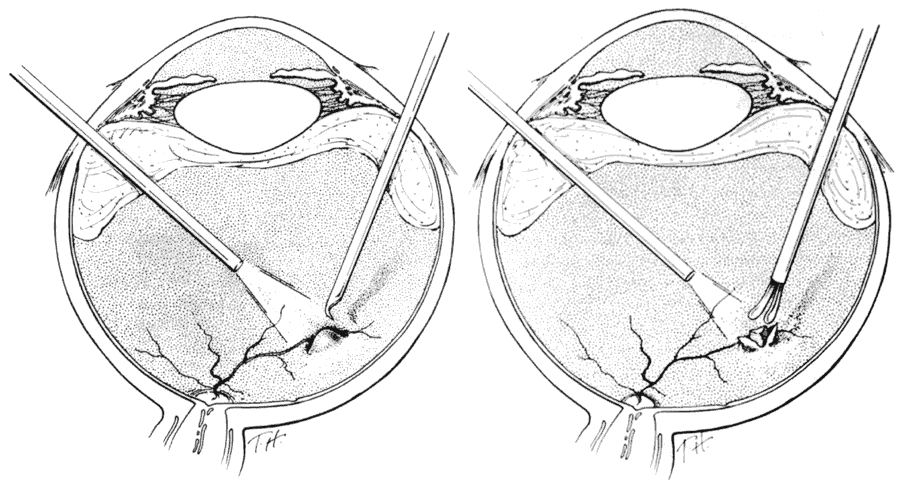

hemorrhage, retinal breaks, and retinal detachment. SUBLUXATION OR DISLOCATION OF THE LENS Minor degrees of subluxation should be suspected when phakodonesis or iridodonesis is noted. Zonular rupture is certain if there is vitreous prolapse into the anterior chamber. In the absence of cataractous changes and related visual impairment, treatment is not indicated. A subluxated, cataractous lens can be removed by aspiration-irrigation or phacofragmentation through a limbal incision, but complications may occur, including posterior dislocation of the lens or lens fragments, vitreous prolapse and incarceration, and vitreous aspiration with resultant vitreous base traction and retinal tear formation. Also, visualization of the anterior vitreous by coaxial illumination is poor compared with fiberoptic endoillumination. These problems make pars plana lensectomy an attractive alternative. Bimanual techniques permit fixation and simultaneous removal of the lens by the vitreous suction-cutter, if the lens is soft, or phacofragmentation if it is sclerotic (Fig. 1A). Posteriorly dislocated fragments can be removed safely, with minimal vitreous traction, using the same incisions and instruments (see Fig. 1B). With endoillumination, prolapsed and juxtalenticular vitreous is readily identified and excised with the vitrectomy probe. Without question, pars plana lensectomy is the preferred method for removing a completely dislocated lens. The technical aspects of dislocated lens and lens fragment removal are described elsewhere in these volumes. VITREOUS HEMORRHAGE Blood in the vitreous may come from tears in the iris, ciliary body, choroid, or retina. Hemorrhage from choroidal ruptures accumulates beneath the neurosensory retina; it then passes through the retina into the vitreous without necessarily causing a retinal break. Regardless, it is important to assume that a retinal break is present until proved otherwise. Vitrectomy is indicated for vitreous hemorrhage caused by ocular contusion when a retinal detachment is suspected because of sudden additional loss of vision, when a retinal detachment is detected through a window in the hemorrhage, when a large retinal break or retinal detachment is diagnosed by ultrasound, or when there is no improvement after a reasonable period of observation. Preoperative contact A-scan and B-scan ultrasonography is helpful for detecting posterior vitreous detachment and differentiating it from retinal detachment. It is dangerous, however, to rely completely upon the accuracy of ultrasound. The presumed posterior hyaloid should be approached with caution until it can be identified with certainty. A standard three-port vitrectomy technique is preferred for nonclearing vitreous hemorrhage. Initially, a central core of opaque vitreous is removed, beginning sufficiently close to the lens that the tips of the cutter and endoilluminator can be visualized. The excision is carried posteriorly, removing successive layers of hemorrhagic and fibrinous vitreous, until the anticipated plane of the posterior hyaloid is approached. A constant surveillance is maintained for a gray membrane containing radially oriented vessels (undiagnosed detached retina). A small opening is made in the detached posterior hyaloid, through which unclotted blood is aspirated by use of active suction from a soft-tipped cannula. Once the retina has been visualized, it is best to remove as much retrohyaloid blood as possible to prevent dispersion into the vitreous cavity with consequent loss of visual control. If the posterior vitreous cortex is not detached, it can be separated from the retina by gentle suction with a soft-tipped cannula at the edge of the optic disc. The elevated cortex is penetrated with a hooked needle or myringotomy blade, creating a window through which a pick is introduced to enlarge the area of cleavage. With the plane between hyaloid and retina established, the surgeon attempts to remove the entire cortical vitreous except for the firmly attached portion at the anterior vitreous base. Cortex that does not separate with gentle manipulation is isolated from surrounding vitreous to eliminate traction on the retina. It is important to remove the cortical vitreous from areas adjacent to retinal breaks. Failure to do so may result in subsequent tangential traction and retinal detachment. A scleral buckle should be considered if retinal breaks cannot be freed from surrounding vitreous cortex. The placement of sclerotomies close to the 3 o'clock and 9 o'clock positions facilitates maximal excision of the hemorrhagic anterior vitreous skirt, thereby improving visualization of the peripheral retina and pars plana. With use of coaxial illumination and scleral depression, the peripheral vitreous on the temporal side of the globe is trimmed with the cutter placed in the temporal sclerotomy, reaching both the superior and inferior quadrants, after which it is transferred to the nasal sclerotomy, and the process is repeated. The fiberoptic endoilluminator may damage the lens if used internally to illuminate the peripheral vitreous on the opposite side of the globe. However, the cone of light from the probe may be directed through the cornea to augment or replace the coaxial light source. Hemorrhagic retrolenticular vitreous can be stripped from the posterior capsule of the lens by gentle aspiration into the cutting port followed by withdrawal of the probe and simultaneous activation of the cutting mode. This technique is dangerous in young children because the retrolenticular vitreous is adherent to the lens, which is sufficiently pliable for aspiration into the port with consequent cataract formation. When the lens is clear, the process of removing peripheral and retrolenticular vitreous is less important than preserving lens integrity in most cases. It is important to expose the peripheral retina and vitreous base because most retinal breaks caused by ocular contusion are located in this area.2 All retinal breaks should be treated. Endolaser is used for posterior breaks, whereas peripheral breaks are treated with indirect laser assisted by scleral depression or transscleral cryoretinopexy. Cryotherapy is preferred when residual opaque vitreous partially obscures the targeted break. Encircling scleral buckles are not necessary after vitrectomy for nonclearing vitreous hemorrhage caused by ocular contusion when a clear view of the fundus periphery reveals no peripheral retinal tears or signs of traction, such as vitreous base avulsion. Similarly, the support of a buckle is usually not needed for treated retinal breaks without retinal detachment. A local scleral buckle should be used when there is residual traction on a posterior break. The peripheral retina should be supported by an encircling scleral buckle when traction on breaks in the oral zone persists or the periphery is poorly visualized because of residual opaque vitreous. RETINAL BREAKS Retinal breaks are created at the time of nonpenetrating blunt injuries3 in 10% to 20% of eyes.3–6 Retinal dialyses are most frequent2–6 and are most often found in the lower temporal (Fig. 2) and upper nasal periphery (Fig. 3).2 Large irregular breaks at the point of impact of blunt trauma are less common but are equally characteristic of nonpenetrating injuries (see Fig. 3).2,7,8 Horseshoe and opercular tears of the equatorial retina (see Fig. 3) are associated with the more characteristic breaks in 25% of eyes.2 Small round holes in atrophic retina at the point of traumatic impact and macular holes (see Fig. 3) are infrequently observed after ocular contusion.2,8 Prophylactic treatment of most traumatic retinal breaks is indicated. Breaks at the point of impact are one exception because they are frequently self-sealing. The surrounding necrotic retina and choroid often unite in a common scar without prophylaxis. It is wise, however, to treat these large tears when scleral depression reveals a slight elevation and movement of their edges and the surrounding retina. Traumatic macular holes also are not treated to prevent additional loss of central vision. They seldom cause retinal detachments when left alone. RETINAL DETACHMENT Although retinal breaks are produced at the time of injury, the retinal detachment may be delayed for months to years because the vitreous gel acts like a tamponade until liquefaction occurs.2 The detachment is typically shallow and slowly progressive because the large volume of vitreous gel in younger eyes prevents bullous retinal elevation as commonly seen in older patients with nontraumatic retinal detachments. Careful preoperative and intraoperative indirect ophthalmoscopy with scleral depression is the key to successful treatment of detachments caused by traumatic retinal dialyses. Small dialyses at the vitreous base borders are difficult to identify, particularly in the upper nasal quadrant where they frequently occur. Breaks of the pars plana epithelium, at the anterior vitreous base border, are less apparent than retinal tears at the posterior edge of the vitreous base. Small dialyses are closed by scleral depression, in which case they are more easily seen on the lateral slopes of the indentation than on its crest. Transscleral cryotherapy is diagnostically helpful. It is not unusual to discover breaks at the vitreous base border for the first time when the edges of the tear are whitened by freezing a suspicious area. It is prudent to treat the entire zone of vitreous base pathology with cryotherapy under direct visual control (see Fig. 3). In this way, treatment of all retinal breaks is assured. The anterior, posterior, and lateral limits of the treated zone are carefully localized and supported by a broad scleral buckle to relieve traction on the entire area. The posterior edge of the dialysis should fall on the crest of the buckle, which must be sufficiently broad to support the anterior edge as well, thereby preventing a recurrent detachment due to anterior leakage. Segments of grooved solid silicone tires are used together with an encircling band, which is positioned on a great circle of the globe to minimize anterior or posterior migration of the buckle. The band is tightened to ensure permanent indentation of the tire segment, but a high encircling buckle is avoided because it promotes posterior gaping or “fish-mouthing” of the dialysis. The band is anchored by a nonabsorbable mattress suture or scleral belt loop in each of the quadrants not occupied by the tire segment. The retinal detachment is often shallow. To avoid retinal perforation or incarceration, subretinal fluid is released through a sclerotomy in an area of sufficient retinal elevation determined by intraoperative indirect ophthalmoscopy with scleral depression. Viewed in profile, the scleral indentation helps gauge the distance between retina and retinal pigment epithelium. To avoid retinal incarceration and blowout, sclerotomies posterior to the buckle should be securely closed after the release of fluid, particularly if additional manipulation of the buckle or an intravitreal gas injection is anticipated. Retinal dialyses in the lower temporal quadrant are often very large, with gaping posterior edges located well behind the equator (see Fig. 2). They are caused by injuries impacting the lower temporal portion of the globe that result in the dissolution and disappearance of retinal tissue.8 In contrast to nontraumatic giant retinal tears with rolled-over retina, they respond favorably to scleral buckling without vitrectomy. A scleral buckle is indicated for smaller dialyses that can be closed with an explant of reasonable size. Very large breaks, as illustrated in Figure 2, are best treated with vitrectomy, gas tamponade, and laser, as recommended for nontraumatic giant retinal tears, rather than with a very large scleral buckle. Traumatic horseshoe and opercular tears are treated with scleral buckling surgery, as are similar nontraumatic retinal breaks. Likewise, traumatic macular holes in detached retina are managed by vitrectomy, internal drainage, and gas tamponade. The use of laser in such cases is controversial but is probably indicated for recurrent detachments and eyes with pre-existing poor central vision due to other traumatic macular damage. |